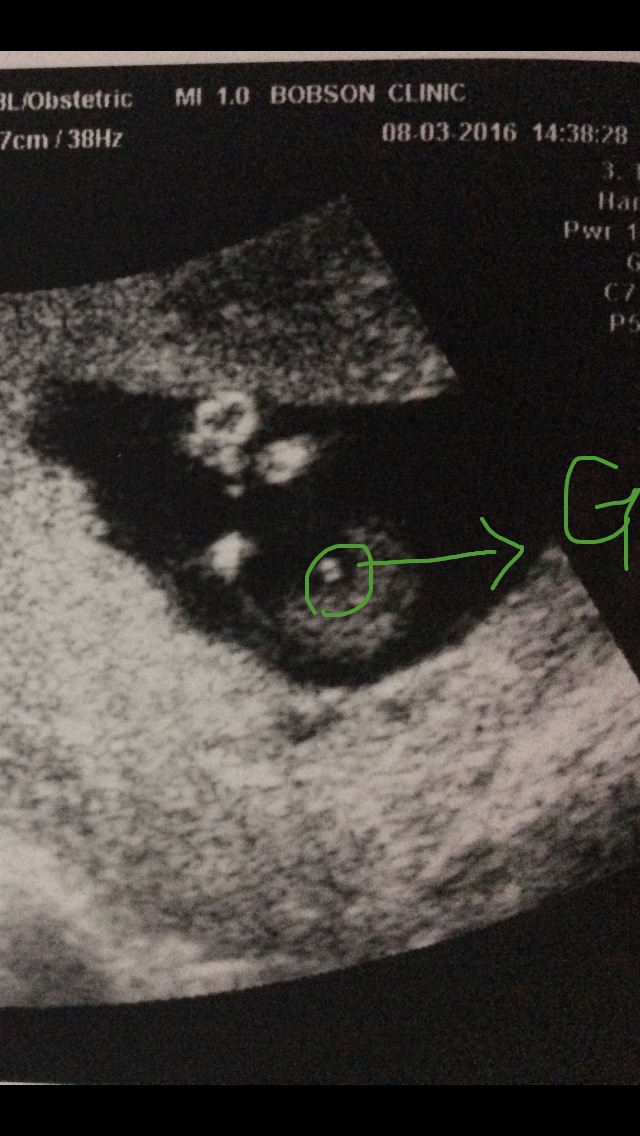

抱歉再補上ㄧ張照片~

寶寶那天平躺腳開開,醫生一直戳白點處

說是雞雞這樣